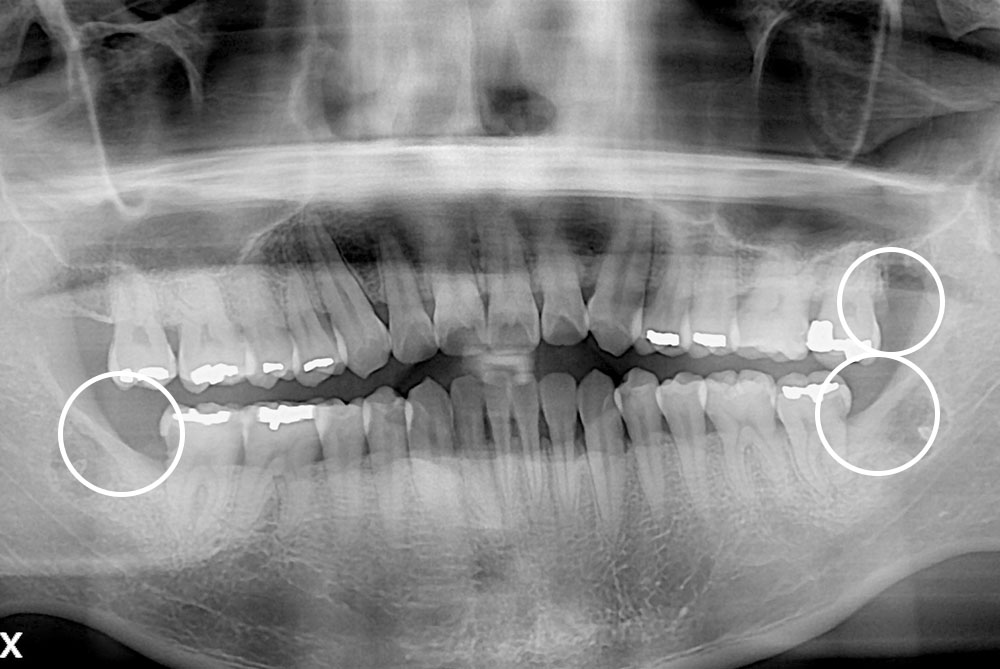

[사랑니] 매복 사랑니 발치

치료후 : 2019-11-12

세종치과는 구강악안면외과학 박사이신 원장님이 발치하는 치과입니다.